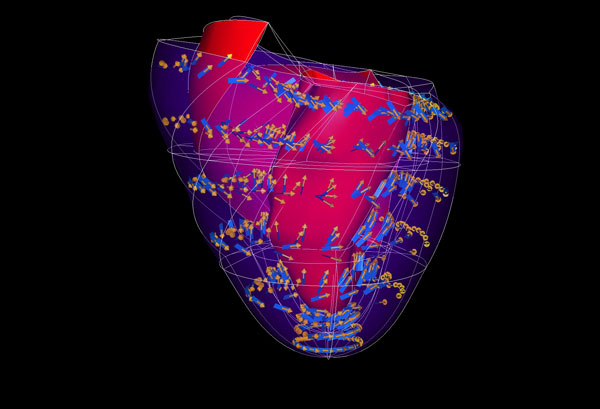

Mapping microscopic worlds

Maurice Wilkins Centre researchers have used unique microscopic imaging techniques to peer into the three-dimensional structure of blood vessel networks – and new computational tec

A new toolkit for building virtual humans (2011)

The Auckland Bioengineering Institute (ABI), established by Maurice Wilkins Centre cofounder Professor Peter Hunter, is a lead player in international efforts to build comprehensiv

Exquisite networks (2011)

Innovative technology developed to study the heart has been adapted for a unique study of the immune system – and will now be applied to cancer, through cross-disciplinary links fo